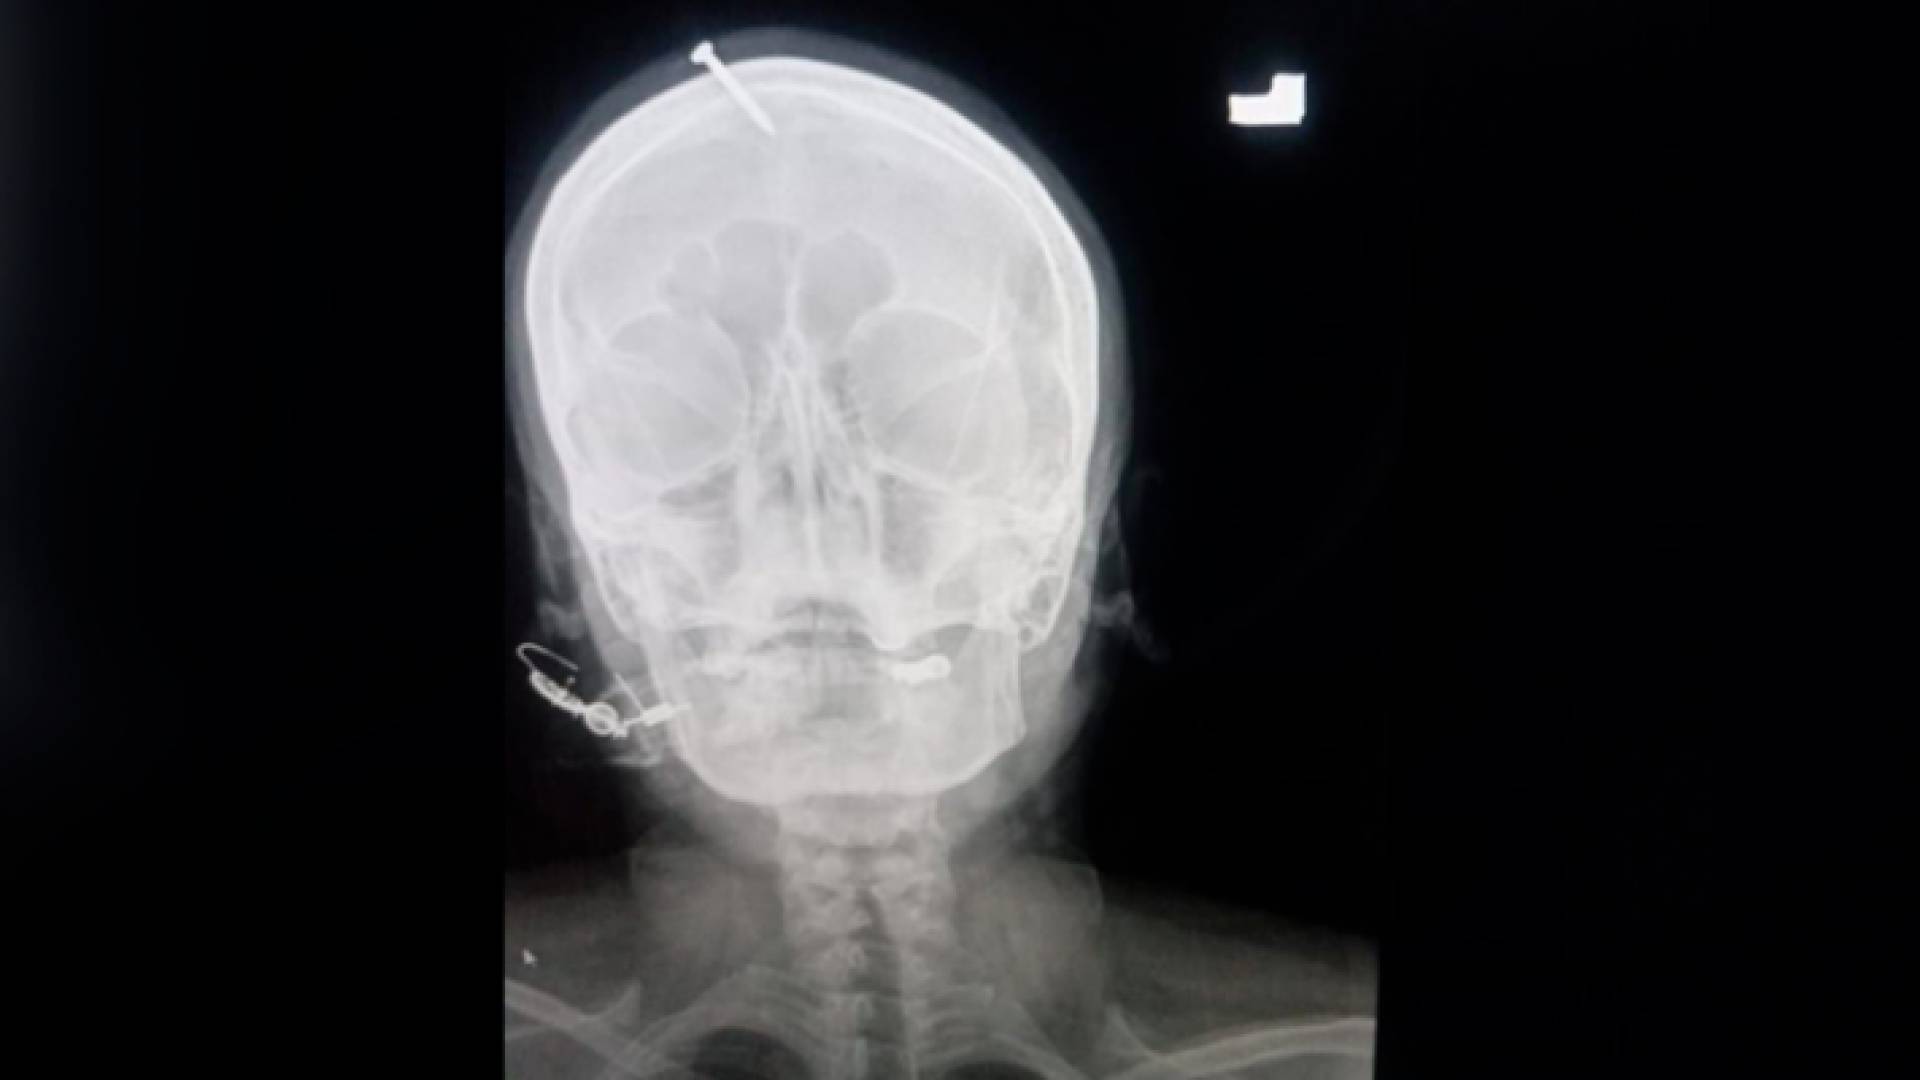

صورة أشعة لرأس المرأة الحامل

وقال الدكتور حيدر سليمان، جراح الأعصاب المقيم، إن المرأة كانت "تنزف" عندما نقلت إلى المستشفى وأن المسمار "تغلغل بعمق" في جمجمتها، مشيرا إلى أن أسرة المرأة حاولت إزالة المسمار في المنزل، ولكنهم فشلوا في ذلك ليتم نقلها إلى المنشأة الطبية، حيث تم إجراء عملية جراحية لها ومن ثم إعادتها.